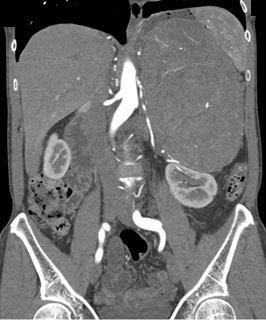

The best dx in this 40ish year old with flank pain is?

lymphoma

adrenal carcinoma

neuroblastoma

cystadenocarcinoma of the pancreas